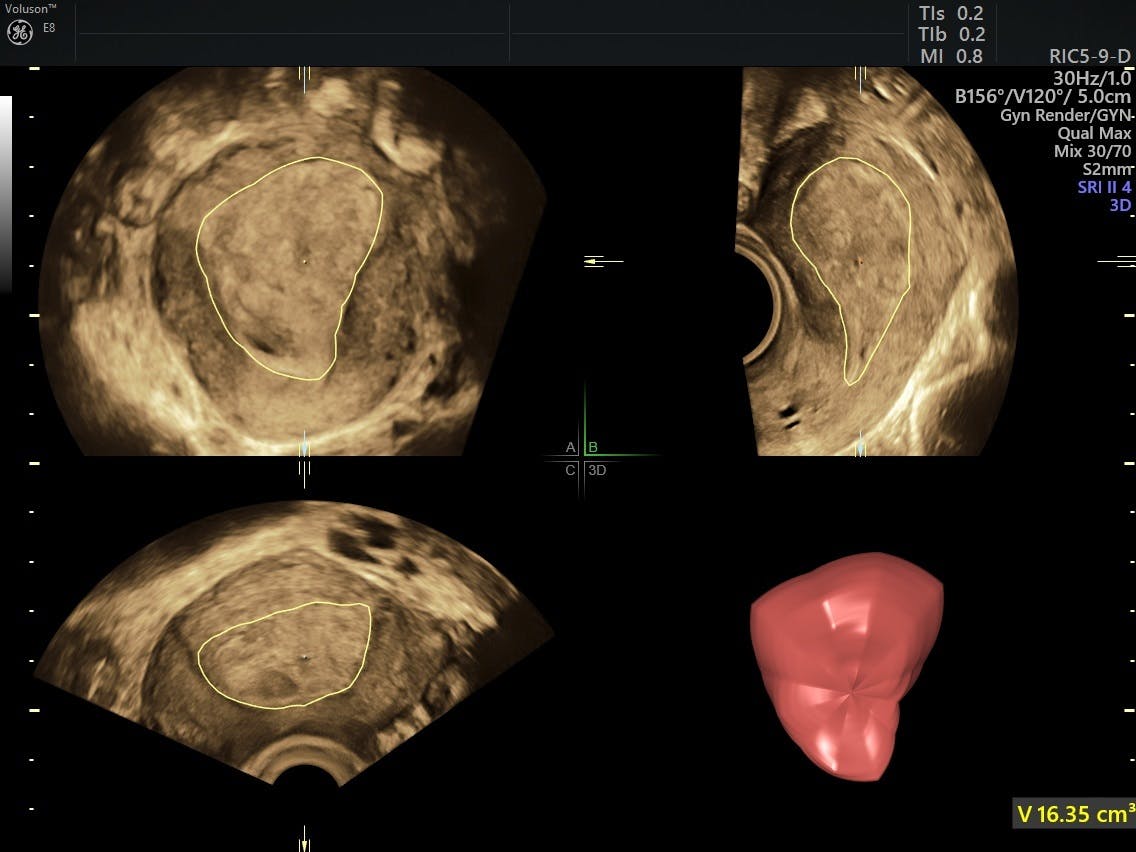

endometrial vaskularitet spiller en avgjørende rolle for å forutsi vellykket embryoimplantasjon, og vurderingen har blitt stadig mer anerkjent som nøkkelen til suksessen til ivf. Et effektivt verktøy for objektivt måling av endometrisk og subendometriell blodstrøm er 3D-ultralyd med fargedoppler, ifølge en studie publisert i Egyptian Journal Of Radiology. Forskerne foreslår at hvis en pasient har ikke-gunstig endometrial blodstrøm sone på dagen for human choriongonadotropin (hCG) administrasjon I IVF eller intracytoplasmatisk sperm injeksjon (ICSI) sykluser, er de usannsynlig å bli gravid og embryo overføring bør avbrytes for å øke sannsynligheten for fremtidig suksess.Selv om endometrievolum er mindre vanlig brukt som en parameter for vellykket embryooverføring, blir klinikere stadig mer interessert i måling ved HJELP AV VOKAL (Virtual Organ Computer-aided AnaLysis) programvare MED 3D ultralyd. Mens forskning fortsetter på dette området, fant EN Studie I Ultralyd I Obstetrik og Gynekologi VOKAL å være et uovertruffen verktøy for kartlegging av konturer og overflate av endometrium og en svært reproduserbar metode når målinger ble tatt under eggstokkstimulering.Forskning publisert I Human Reproduction, i mellomtiden, fant at graviditet og implantasjonsrater var signifikant lavere hos pasienter med et endometrisk volum på mindre enn 2 ml. Et lavt endometrisk volum kan til og med forutsi graviditetstap hos kvinner som gjennomgår IVF.

Beregning Av Endometrialvolum Ved BRUK AV VOKAL

i 2018 fant forskerne at endometrievolumet var betydelig større på begge SIDER.dagen for hcg utløser hos kvinner som senere ble gravid enn hos de som ikke gjorde det. Andre studier har imidlertid funnet at endometrialvolum er en mindre pålitelig prediktor for graviditet enn andre faktorer som vaskularitet.